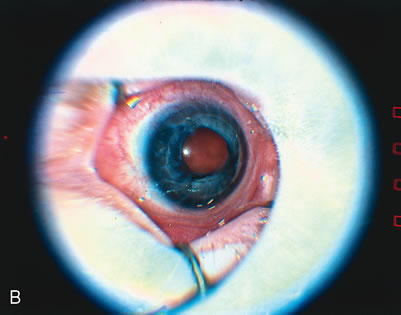

COMPLICATIONS AND THEIR MANAGEMENT

The complications of scleral buckling surgery for ROP are similar to those that can occur with adult scleral buckling surgery, with some special considerations for the infant eye. The premature infant's eye is significantly smaller than an adult eye. Full adult size of the globe is not attained until 3 years of age. An infant at 34-weeks' gestation has an eye that is 15 mm in diameter (Fig. 9). The sclera of the infant eye is thin, and the surgeon must be especially careful when depressing, cutting a bed, and passing sutures.

Fig. 9. Gross specimens of an adult eye (A) and a 34-week-gestation infant eye (B). (Courtesy of James P. Bolling, MD, Mayo Clinic, Jacksonville, FL)